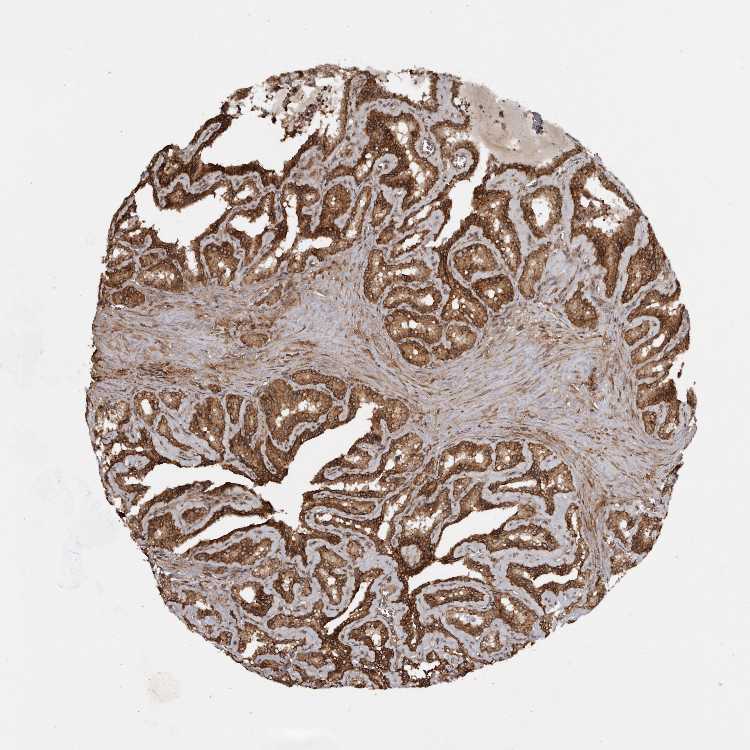

TISSUE PRIMARY DATA SEMINAL VESICLE Show tissue menu

SEMINAL VESICLE - Antibody stainingi

Antibody staining in the annotated cell types in the current human tissue is reported as not detected, low, medium, or high, based on conventional immunohistochemistry profiling in selected tissues. This score is based on the combination of the staining intensity and fraction of stained cells.

Each image is clickable and will lead to virtual microscopy that enables deeper exploration of all samples and also displays staining intensity scores, fraction scores and subcellular localization as well as patient and tissue information for each sample.

Antibody HPA027409Antibody HPA027453Antibody HPA030058

Glandular cells HighMediumMedium